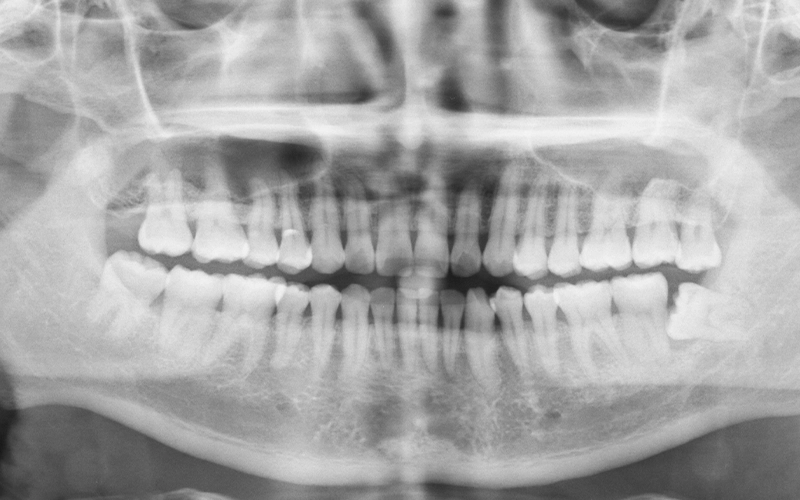

Our skilled team at Moorooka Square Dental takes a gentle and careful approach to wisdom teeth extractions. Using advanced imaging and modern techniques, including an Orthopantomogram (OPG) X-ray, we can see exactly how your teeth are positioned and plan your treatment with precision for a safe, smooth procedure.

Wisdom Teeth Extraction Xray